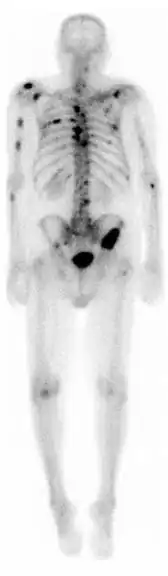

A nuclear medicine whole-body bone scan. The nuclear medicine whole-body bone scan is generally used in evaluations of various bone-related pathology, such as for bone pain, stress fracture, nonmalignant bone lesions, bone infections, or the spread of cancer to the bone.

Bone scan showing multiple bone metastases from prostate cancer.